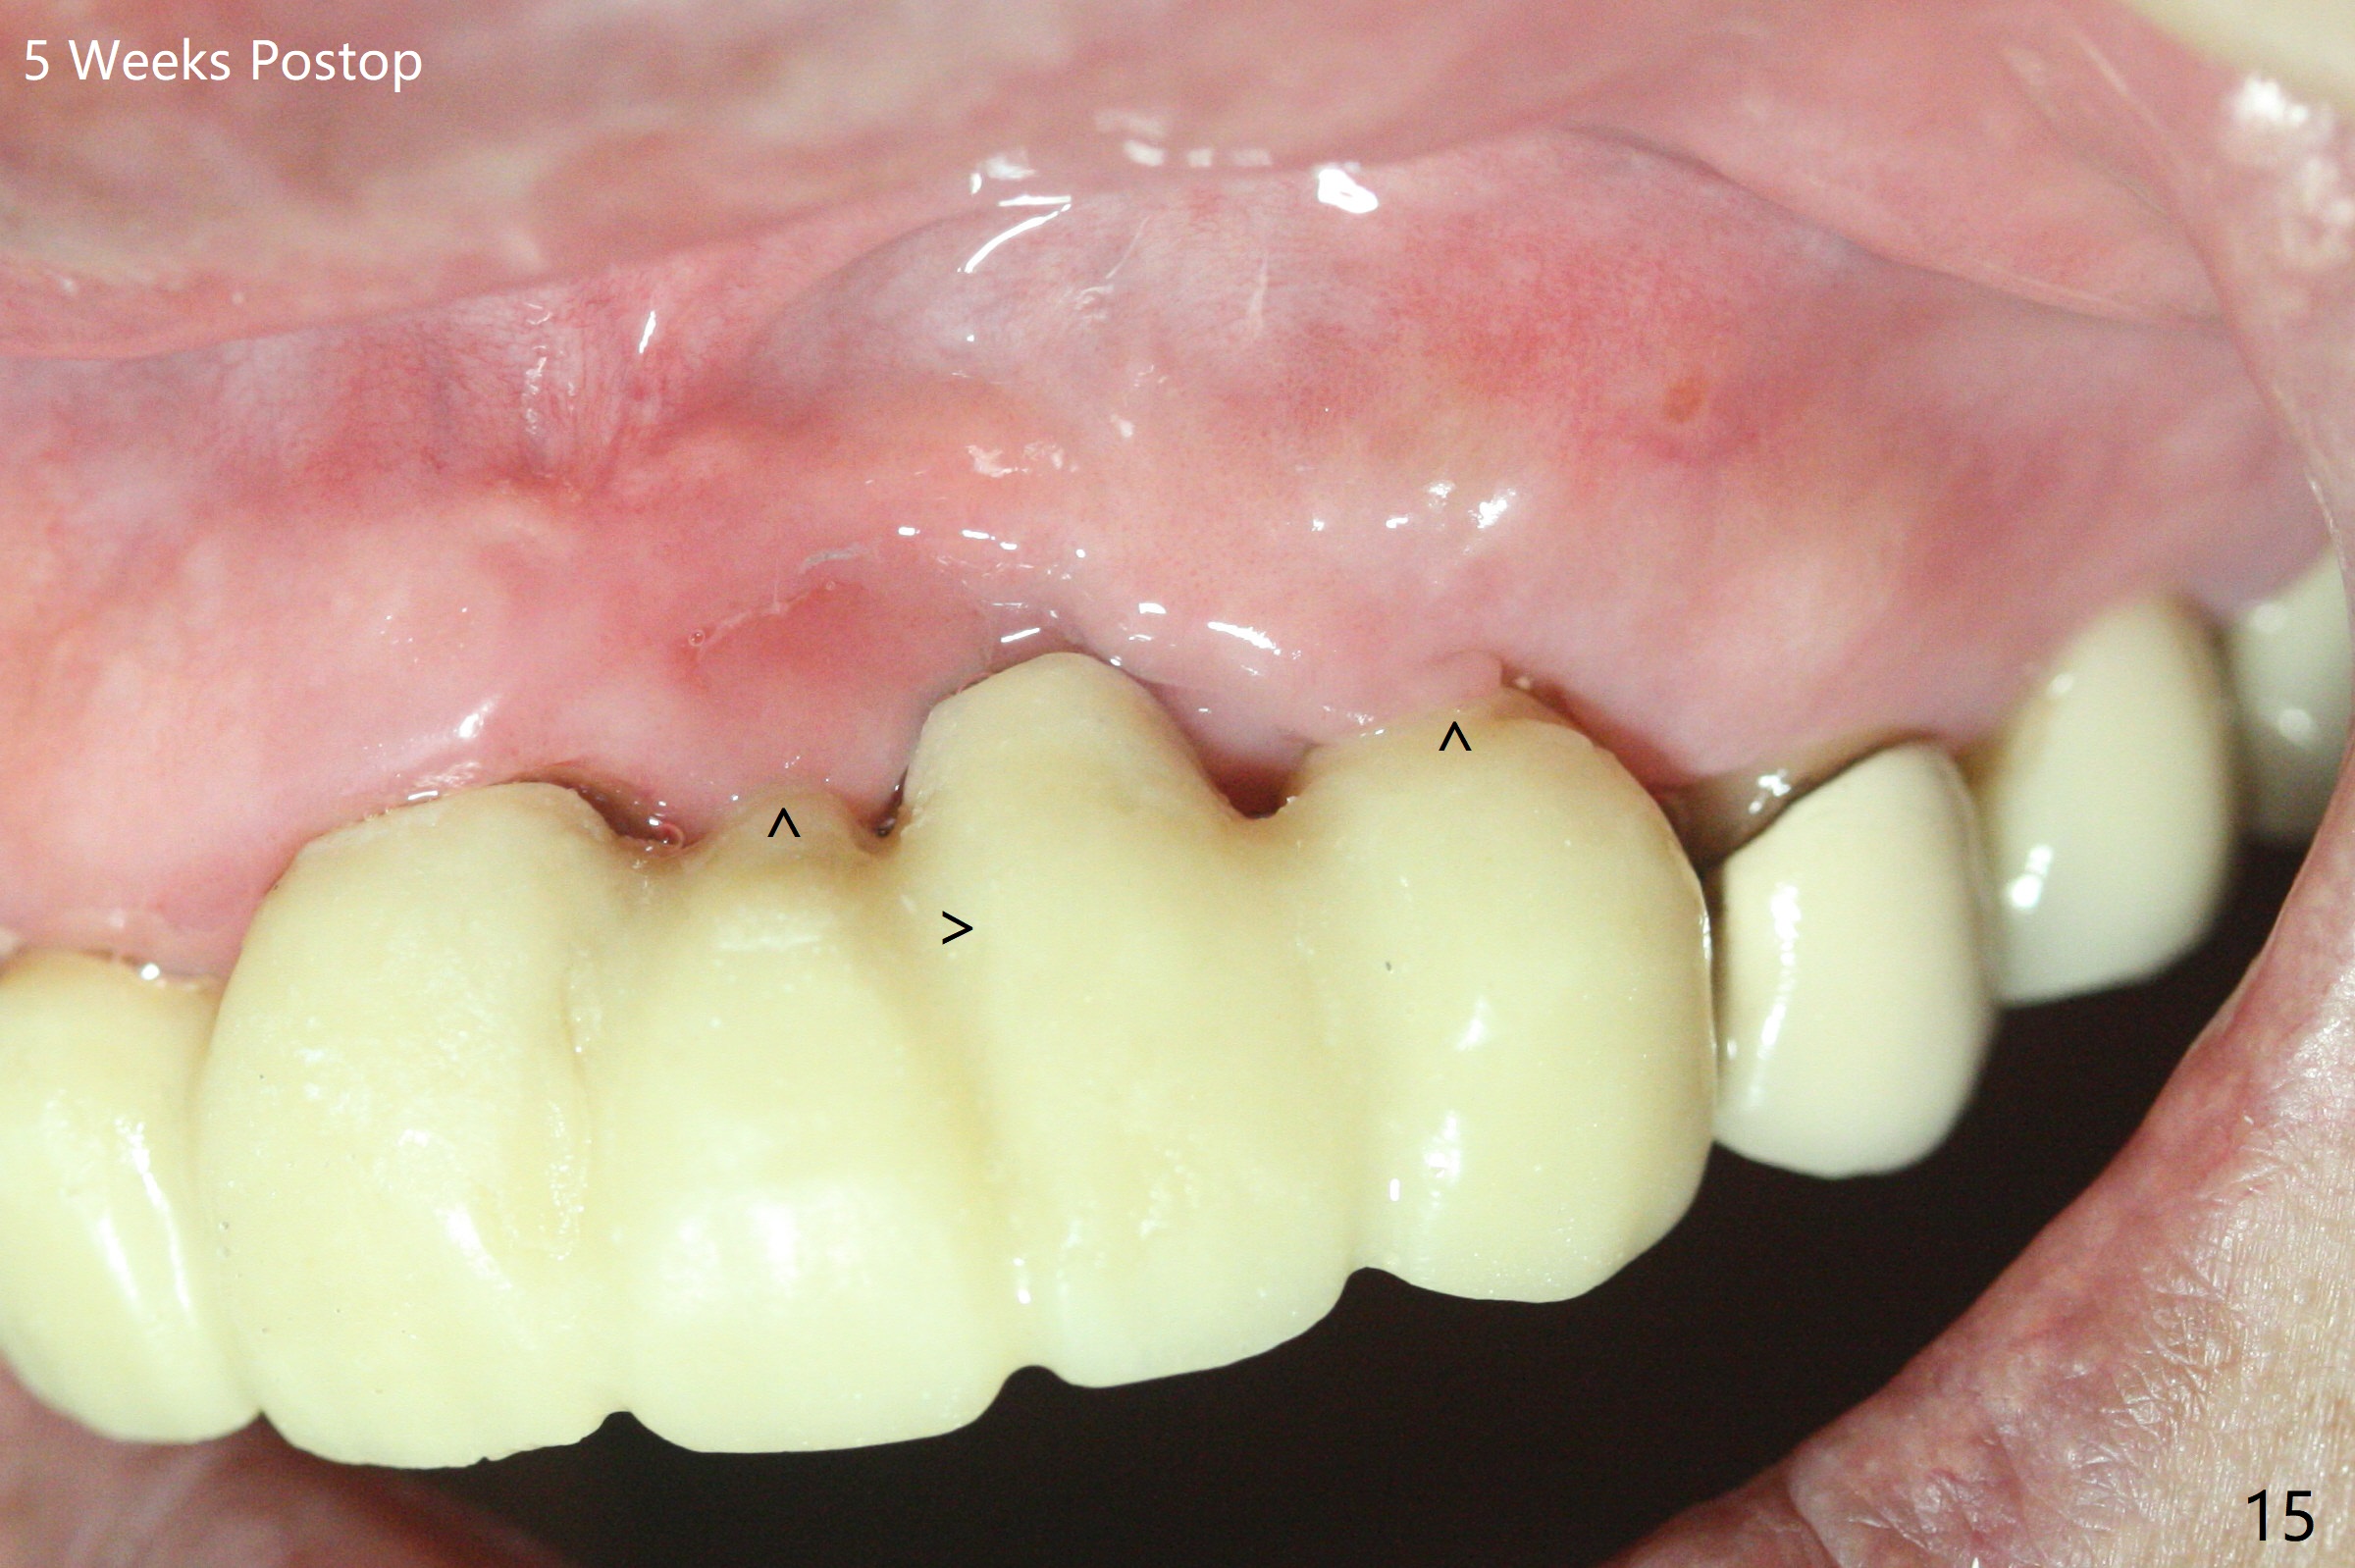

The mesiobuccal margin at #8 is redefined 4 weeks postop (Fig.14) so that the cervical end of the temporary crown is able to move mesially (Fig.13). The most coronal portion of the bone graft at #11 begins to be detached (*). The mesial portion of the abutment at #10 will be removed (curved white line) in the following week. After removing the most coronal portion of detaching bone graft at #11, acrylic is added to form a concave pontic (Fig.15 ^). With removal of the mesial portion of the abutment at #10, the retainer is moved distal (>). Pontics form at UL1 and 3 two months postop (Fig.16 *), while there is buccal atrophy at UL1,2 (Fig.17). 术后3个月植牙区牙龈形态良好(图十八),即将暴露,放置愈合基台。图十九是在右上1根管治疗时(基台放置后五天)拍摄。左上3术后3个月3个星期,1,2唇侧塌陷(图二十)。叶状植体处牙槽嵴往根尖萎缩(图二十一:^)。尽管做了松弛切口,放入事先预备的粘性骨粉后,几乎没有空间放置结缔组织移植物,恰好还没有取。放置PRF膜后,使用4-0 Monoglyc缝线缝合。牙龈似乎冠方移位(图二十二:箭头)。植骨后,唇侧仿佛饱满多了(图二十三:*)。骨粉放置于左上1,2唇侧和牙槽嵴(图二十四:*,与之前(图十九)对比)。后者有助于牙龈冠方移位,而前者有助于增加唇侧饱满度。植骨术后两周唇侧仍饱满(图二十五,六)。植骨后四个月牙冠粘固,两个月后,病人抱怨10号牙左右食物坎塞(图二十七),9/10牙冠撤除,10基台边缘加深,重做临时牙冠,同时增加9凹陷(pontic)。一个月后,9/10临时牙冠修整两次,11永久性牙冠撤除,也制备临时牙冠,外形明显改善(图二十八)。